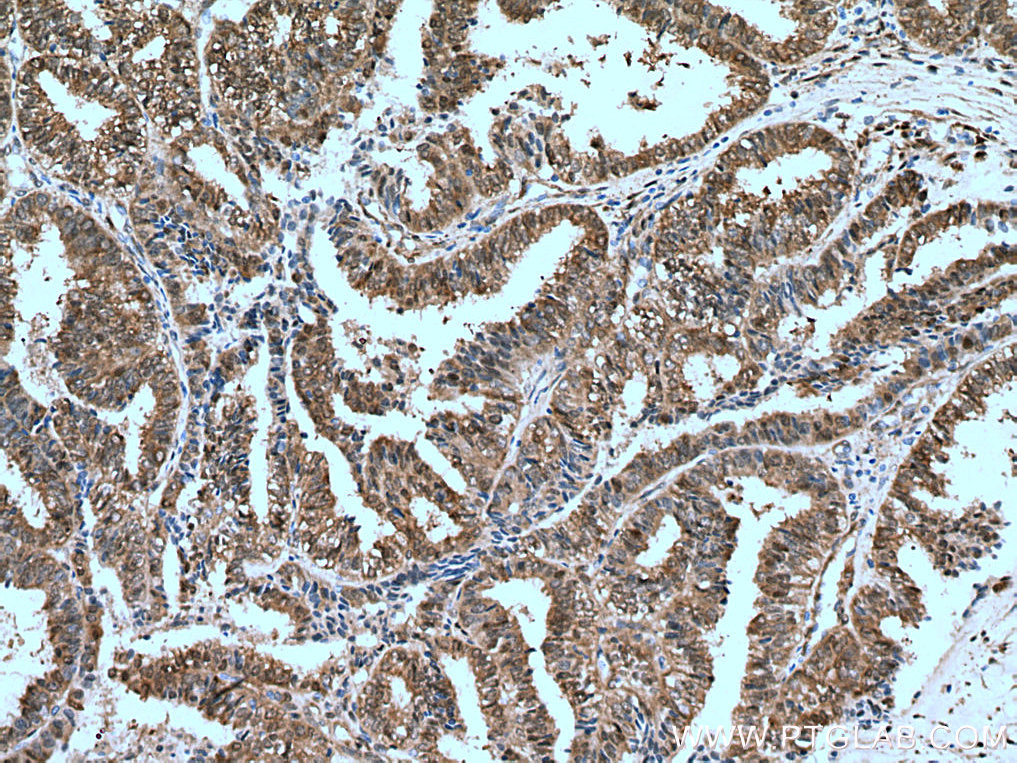

| Positive IHC detected in | human lung cancer tissue, human colon cancer tissue, human liver cancer tissue, human ovary tumor tissue Note: suggested antigen retrieval with TE buffer pH 9.0; (*) Alternatively, antigen retrieval may be performed with citrate buffer pH 6.0 |

| Immunohistochemistry (IHC) | IHC : 1:1000-1:4000 |